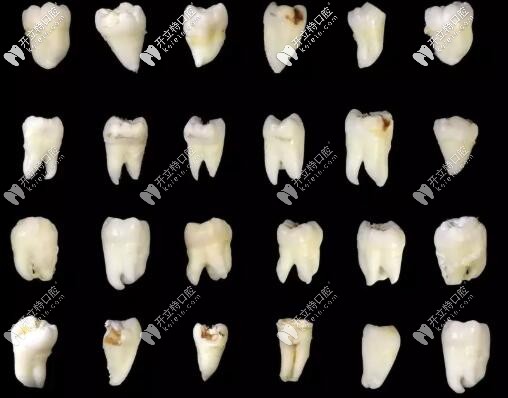

智齒的各種形態(tài)

這是某位醫(yī)生拔過的智齒